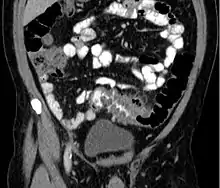

People with the above symptoms are commonly studied with computed tomography, or CT scan.[12] The CT scan is very accurate (98%) in diagnosing diverticulitis. In order to extract the most information possible about the person's condition, thin section (5 mm) transverse images are obtained through the entire abdomen and pelvis after oral and intravascular contrast have been administered. Images reveal localized colon wall thickening, with inflammation extending into the fat surrounding the colon.[13] The diagnosis of acute diverticulitis is made confidently when the involved segment contains diverticula.[14] CT may also identify people with more complicated diverticulitis, such as those with an associated abscess. It may even allow for radiologically guided drainage of an associated abscess, sparing a person from immediate surgical intervention.

Diverticulitis on CT scan in coronal view